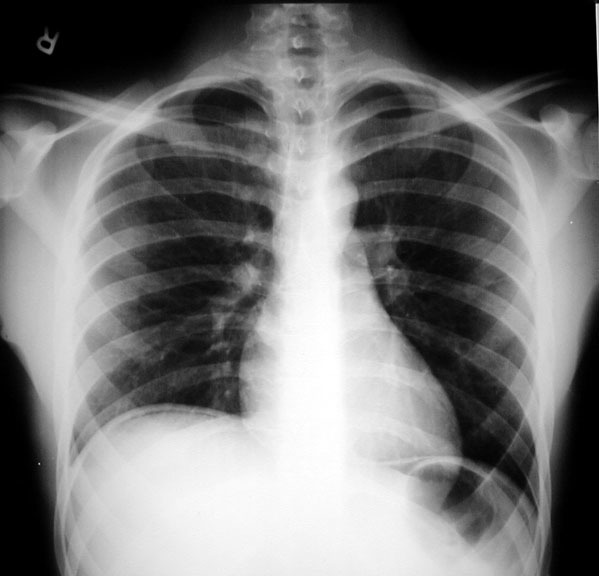

Describe the abnormality/ies

Cardiomegaly